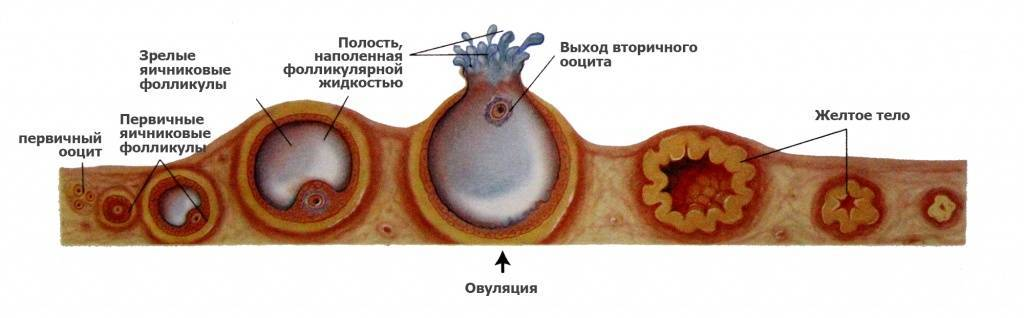

Созревание фолликула в яичнике: этапы и процессы

Раздел: Другие животные